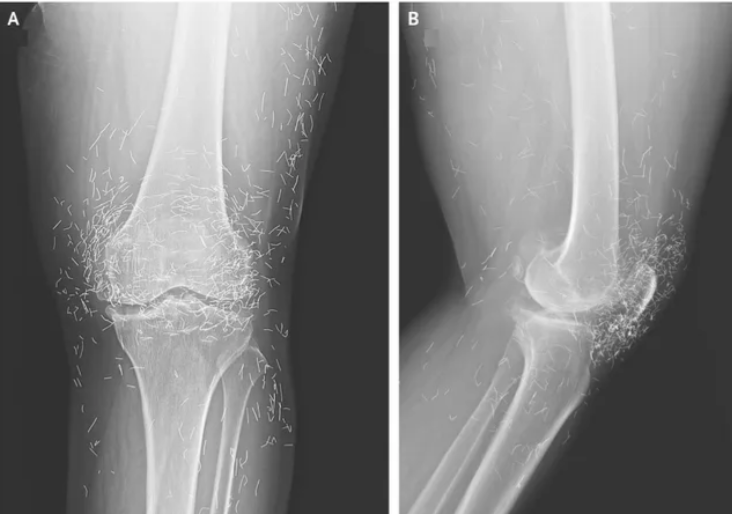

ألم شديد في ركبة امرأة يكشف عن “خيوط ذهبية” في مفاصلها